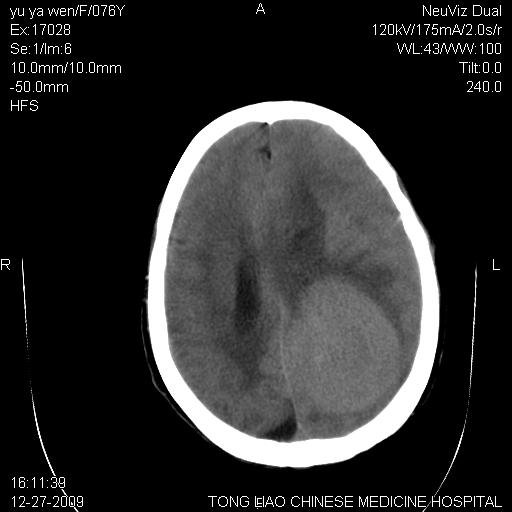

以下是引用lizhiguang在2009-12-27 19:06:00的发言:[br]脑膜瘤

以下是引用zhao_bin2008在2009-12-27 20:34:00的发言:[br]考虑脑膜瘤,伴肿瘤出血,建议增强检查

以下是引用zsl6918在2009-12-27 19:28:00的发言:[br]建议对症治疗后强化检查,考虑脑膜瘤可能性大。